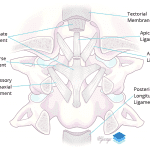

- Offset of the lateral masses of C1 with respect to the occipital condyles consistent with atlanto-occipital subluxation

- Bilateral atlanto-occipital subluxation (extensive ligamentous injury subsequently confirmed on MRI)

Offset of the lateral masses of C1 with respect to the occipital condyles concerning for ligamentous injury. Recommend MRI for further evaluation.